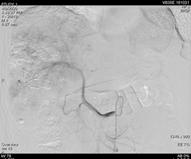

2019年1月17日(术后1个月)入院复查,影像学见疑似复发病灶。                         图片

图:影像学检查(2019-01-17)

遂予肝动脉化疗栓塞(TACE)治疗,行数字减影血管造影(DSA)可见肝右叶多个结节状肿瘤染色,明确肝左、右动脉分支为肿瘤供血动脉,判定为外科术后复发。

图片

图:第一次TACE治疗